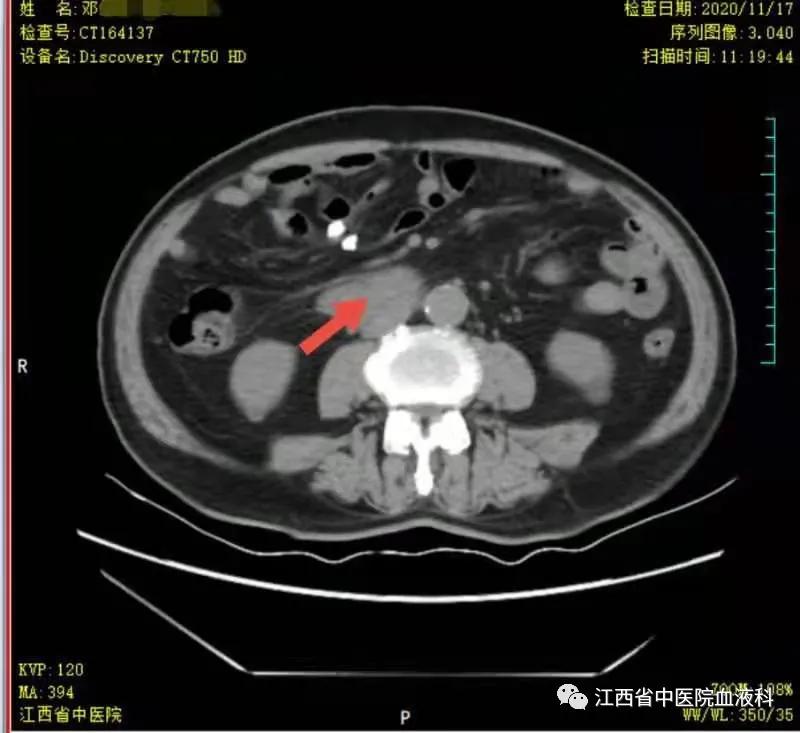

2020年10月中旬邓大爷在家人的陪同下来我科就诊,全腹部增强CT提示:右侧*丸睾**切除术后复查:1.腹膜后(胰头后下方)、双侧肾上腺区团块状异常强化影。2.肝左内叶上段小囊肿,双肾小囊肿,较前相仿。3.右侧腹股沟前方、皮下条索、小片影,境界不清,较前减小,拟为术后改变。4.右下腹腔少许钙化淋巴结,较前相仿。因病情危急,考虑邓大爷高龄、体能差、窦性心动过缓(平均心率50次/分)心脏功能差等情况,经讨论于2020-10-24起第一次行减剂量方案R-miniCHOP(利妥昔单抗700mg d0、环磷酰胺700mg d1、多柔比星40mg d1、长春瑞滨20mg d1、地塞米松10mg d1-5)方案。第一次化疗后评估病情,腹腔瘤体缩小了2/3,取得了很好的治疗效果,可邓大爷心脏却亮起了红灯,经过了积极护心等支持治疗后,大爷心脏功能有所恢复。遂于2020-11-19、2020-12-10行2次R-miniCOP方案(去除了具有心*毒脏**性的多柔比星),三次化疗结束后予评估病情,提示腹腔包块明显缩小,淋巴瘤病情有所好转(见图1至4)。

图1 化疗前腹腔瘤块